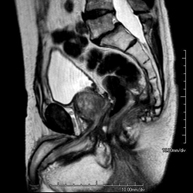

Prova diagnòstica no invasiva que consisteix en l'obtenció d'imatges d'alta definició anatòmica de l'abdomen mitjançant l'ús d'un camp electromagnètic i ones de ràdio (amb un emissor i un receptor). No utilitza radiació ionitzant. En aquesta exploració s'inclouen el fetge, el pàncrees, la melsa, la via biliar, la vesícula biliar, les glàndules suprarenals, els ronyons, l'aorta abdominal, la vena cava inferior, l'estómac, el duodè, etc. En alguns casos caldrà emprar contrast paramagnètic (Gadolini) per caracteritzar les lesions. - RM Pelvis femenina

Prova diagnòstica no invasiva que consisteix en l'obtenció d'imatges d'alta definició anatòmica de la pelvis mitjançant l'ús d'un camp electromagnètic i ones de ràdio (amb un emissor i un receptor). No utilitza radiació ionitzant. Es realitza per a l'estudi de patologies d'úter, d'ovari, de trompes i de vagina, ja siguin d'origen tumoral, inflamatori o vascular. També permet valorar les estructures adjacents localitzades a la pelvis i la identificació de les seves alteracions. De vegades és necessari l'ús de contrast intravenós (Gadolini) per caracteritzar les lesions. - RM Pelvis masculina

Prova diagnòstica no invasiva que consisteix en l'obtenció d'imatges d'alta definició anatòmica de la pelvis masculina mitjançant l'ús d'un camp electromagnètic i ones de ràdio (amb un emissor i un receptor). No utilitza radiació ionitzant. No requereix preparació prèvia. En algunes ocasions necessita l'ús de contrast paramagnètic (Gadolini) per caracteritzar les lesions. Aquesta prova permet valorar òrgans com la bufeta urinària, la unió entre els urèters i la bufeta, la pròstata, les vesícules seminals, la uretra i els ossos de la pelvis, entre d'altres. - RM de Fetge

- URO-RM

Prueba diagnóstica no invasiva que consiste en la obtención de imágenes de alta definición anatómica del sistema urinario mediante el empleo de un campo electromagnético y ondas de radio (con un emisor y un receptor). No utiliza radiación ionizante. Requiere el uso de contraste paramagnético (Gadolinio) que se excretará por el sistema urinario y nos permitirá obtener imágenes en 2D y 3D. - RM Próstata